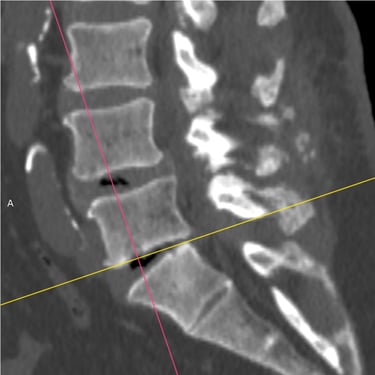

Columna lumbar inestable con listesis: tratamiento con artrodesis y tornillos transpediculares

La listesis lumbar ocurre cuando una vértebra se desplaza hacia adelante o hacia atrás respecto a la vértebra inferior, generando inestabilidad de la columna lumbar. Esta condición puede causar dolor lumbar crónico, compresión nerviosa, ciática, debilidad en las piernas o dificultad para caminar. Cuando el tratamiento conservador no es suficiente, la artrodesis lumbar con tornillos transpediculares es una alternativa quirúrgica eficaz. Este procedimiento permite fijar las vértebras afectadas mediante implantes que estabilizan la columna y favorecen la fusión ósea. Con técnicas modernas y abordajes mínimamente invasivos, se logra aliviar el dolor, mejorar la estabilidad vertebral y recuperar la función del paciente.